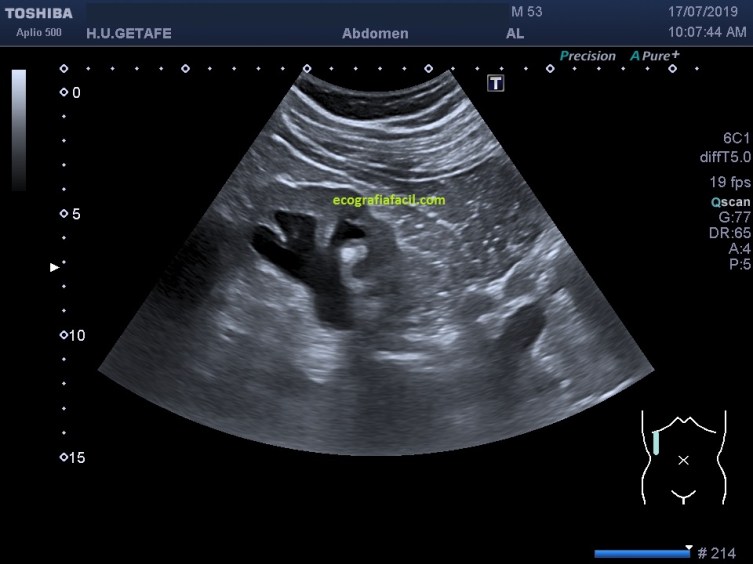

En la imagen 4,5 y 6 ves clarísimamente una dilatación renal, cómo los cálices están dilatados, y que están todos unidos y son confluentes (flechas amarillas imagen 4) con la pelvis renal. Cuando lleguemos a la pelvis renal como te enseño en la imagen 4 marcado en rosa debemos continuar por el uréter con objeto de intentar seguirlo y poder demostrar el origen de esa posible obstrucción, en la imagen 6 puedes verlo.

6